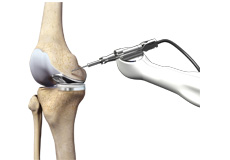

Knee Arthoscopy

Knee Arthroscopy is a common surgical procedure performed using an arthroscope, a viewing instrument, to diagnose or treat a knee problem. It is a relatively safe procedure and most of the patients are discharged from the hospital on the same day of surgery.

Knee Replacement with OrthAlign Technology

Image Courtesy: www.orthalign.com

OrthAlign® uses a technology that simplifies and enhances the precision in implant alignment, significantly improving procedure outcomes.